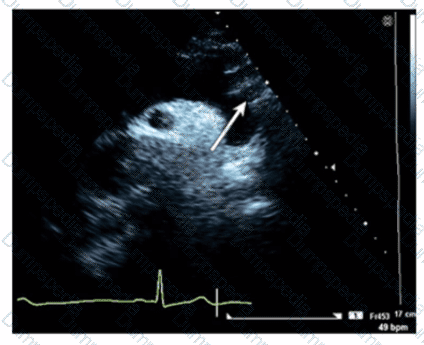

Which region of the aorta is being measured to assess the critical finding in this image?